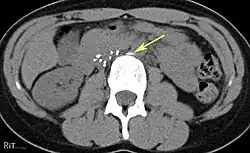

Of these IVC filter side effects, 328 involved device migration, 146 involved embolizations after detachment of device components, 70 involved perforation of the IVC, and 56 involved filter fracture. Much of the medical community believes that this large number of adverse events is related to the heart filter remaining in place for longer than necessary.

- Perforation of the vena cava

- 9% (12 of 132 patients) delayed filter penetration of the IVC greater than 3 mm